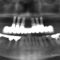

インプラントの埋め込み手術から4ヶ月の治癒期間を待ち最終的なジルコニア性の歯を製作しました。

治療期間中は仮歯をご用意しておりましたので治療もスムーズにすすみ最終的なジルコニア性の歯が入ったときも違和感なく治療の終了ができました。治療期間中は固定式の仮歯と着脱式の仮歯がございます。奥歯1本など仮歯が審美的にも不必要な部分には通常は使用しません。